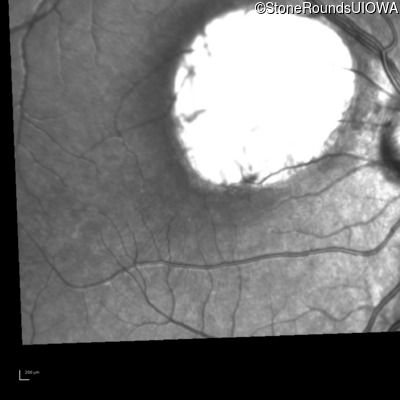

Retinoblastoma (IIID2)

Age at visit: 2 weeks

Age at visit: 5 weeks (Visit 2)